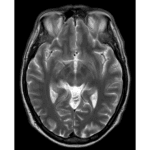

Announcing a new article publication for Zoonoses journal. This study was aimed at reviewing a case series of 35 patients with neuroinvasive Toscana Virus (TOSV) infections, to evaluate clinical findings and outcomes. A retrospective analysis was conducted in two secondary referral facilities in Italy. Patients with confirmed TOSV infection were included. Biochemical and serological analyses […]